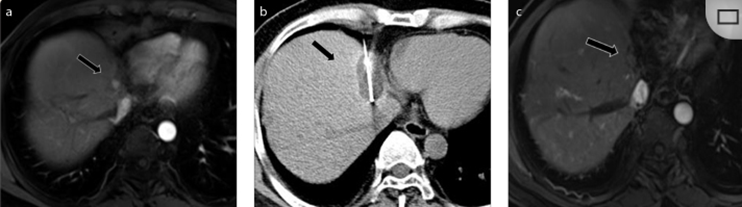

79 歲男性,肝轉(zhuǎn)移(結(jié)直腸癌)腫瘤的完全消融病例

( a ) 軸向 MRI 和 ( b ) 軸向 CT 顯示肝S8段有一個(gè)16mm的病灶,鄰近肝緣。( c )冷凍消融期間CT顯示放置了2個(gè)冷凍探針,低密度冰球包圍病灶。(d)術(shù)后1個(gè)月隨訪 CT顯示冰球?qū)?yīng)的壞死區(qū)域,未見復(fù)發(fā)。(e)術(shù)后6個(gè)月的CT,壞死區(qū)域縮小,未見復(fù)發(fā)。(f)與基線影像(g)相比,12個(gè)月后的FDG-PET/CT顯示未見FDG攝取。

62歲女性,肝轉(zhuǎn)移(卵巢癌)腫瘤的完全消融病例(a)軸向CT顯示病變位置毗鄰心臟和上腔靜脈(黑色箭頭)。(b)術(shù)中軸向CT掃描:使用三個(gè)冷凍探針。1個(gè)月后的軸向(e)和冠狀位(f)增強(qiáng)CT掃描顯示低密度區(qū)域,由于肉芽組織反應(yīng)引起的邊緣增強(qiáng)。

技術(shù)成功100%,92% 的病灶中觀察到腫瘤完全消融。16 名患者 (33%) 出現(xiàn)局部復(fù)發(fā)。10 名患者 (20%) 因局部復(fù)發(fā)或腫瘤消融不完全而接受二次冷凍消融術(shù)。

7名患者出現(xiàn)輕微并發(fā)癥,未發(fā)現(xiàn)膿腫形成、膽漏、膽汁瘤或血液學(xué)變化。冷凍消融可安全、有效治療毗鄰重要臟器的原發(fā)性肝臟腫瘤和肝轉(zhuǎn)移瘤患者,有效控制腫瘤局部進(jìn)展,使患者生存獲益。我國作為肝癌大國,對于肝癌的治療一直給予高度重視?;趯<夜沧R和相關(guān)文獻(xiàn)研究結(jié)果顯示,冷凍消融技術(shù)具有高效、低成本、創(chuàng)傷小、適應(yīng)證廣、并發(fā)癥相對較少等優(yōu)點(diǎn),可有效延長患者生存期、提高生活質(zhì)量、降低患者經(jīng)濟(jì)負(fù)擔(dān)。因此,冷凍消融技術(shù)在肝癌的應(yīng)用中有著極高的潛力和廣泛的發(fā)展空間。